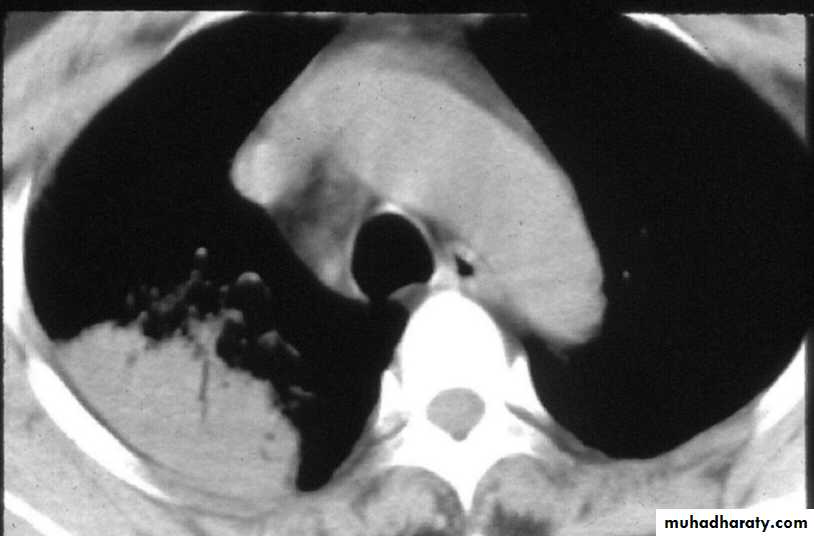

Para-pneumonic effusion-commonEmpyema

Suppurative pneumonia/lung abscess-see below

ARDS, renal failure, multi-organ failure

Ectopic abscess formation (Staph. aureus)